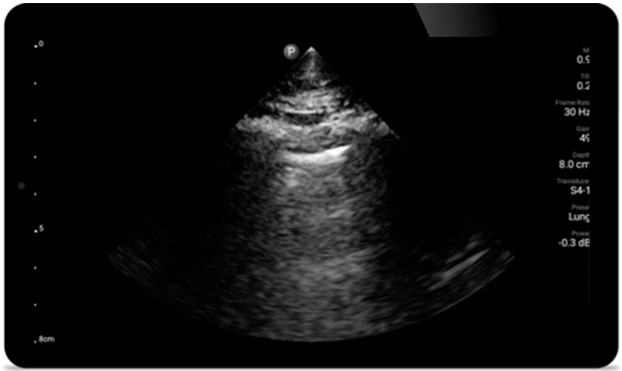

Gebruik Lumify voor luchtweg- en pulmonale beoordeling

De Lumify POCUS-oplossingen kunnen u helpen de endotracheale tube binnen de trachea te detecteren, ondersteuning te bieden bij urgente coniotomieprocedures, en diagnoses te stellen van pleurale effusie en interstitiële alveolaire ziekten.

Pulmonale beoordeling